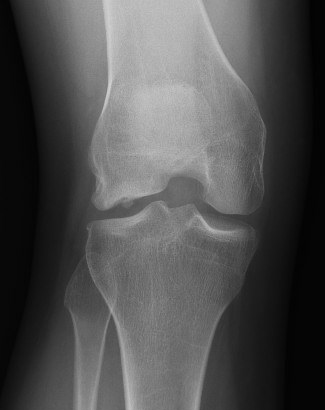

Preoperative Planning

AP full length standing xrays

Line from centre of talus to desired mechanical axis

Line from centre of femoral head to desired mechanical axis

a) is the desired angle of correction

Valgus OA Preop PlanningDFVO preopDistal Femoral Osteotomy Postop View